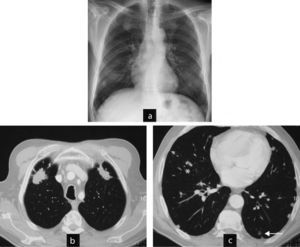

This patient was a 56-year-old woman, diagnosed with RA 5 years prior, smoker, and positive RF. A chest X-ray taken due to chest pain detected lung nodules. Computed tomography of the thorax found rounded nodules of 1–2cm cavitated, progressing in size and complicated by a pneumothorax. She underwent node resection surgery and an open pleural biopsy with a diagnosis of rheumatoid nodules. In subsequent tests all nodules disappeared.

Cases 2 and 3. Evolution of cavitated nodules. (a) and (b) Case 2: cavitated rheumatoid nodules that increase in size. The case was complicated and open pneumothorax produced a cavitated nodule on the pleura (pneumothorax image not shown). (c) and (d) Case 3: rounded subpleural nodules, in a patient with signs of interstitial lung disease. Control computed tomography of nodules show a slight decrease in size and cavitation (arrow).

This was a 53-year-old patient, diagnosed with palindromic rheumatism 6 years prior, and a smoker. RF has slowly turned positive. Interstitial lung disease associated with no respiratory symptoms. In a control CT, we detected, rounded subpleural lung nodules. Monitoring was proposed and computed tomography at 6 months shows that the nodules decreased in size and one of them had cavitated.

Case 4 (Fig. 3)This patient was a 66-year-old male, diagnosed with RA for 9 years, RF positive and an ex-smoker. A year ago he was diagnosed with interstitial lung disease with respiratory symptoms, moderate dyspnea and mild restrictive respiratory failure. A control CT detected, one year later, rounded subpleural pulmonary nodules. The patient required follow-up.

Cases 4 and 5. Different clinical settings: surgical biopsy or control image. (a) Case 5: chest CT: non-specific nodules in a patient without a diagnosis of joint disease and respiratory symptoms. The patient was diagnosed with necrotizing granulomas requiring surgical biopsy. The patient developed rheumatoid arthritis a year later. (b) Case 4: CT scan of the chest: nodules with typical radiological aspect of rheumatoid nodules, rounded, subpleural and multiple in a patient with rheumatoid arthritis associated with interstitial lung disease. Control image.